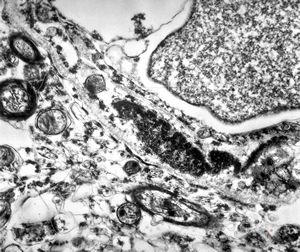

M,3y. | globoid leukodystrophy of Krabbe - n.suralis